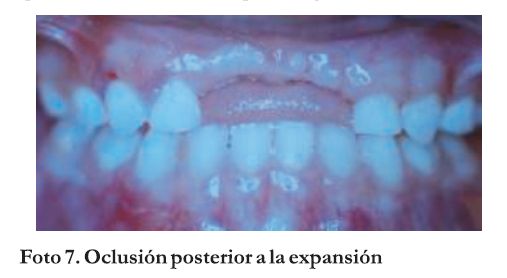

En el examen clínico y radiográfico se evalúa la necesidad o no de la colocación de una mantenedor de espacio para la zona incisiva anterior (reponiendo los dientes 51 y 61). Sin embargo, se llega a la conclusión que se ha mantenido la expansión maxilar lograda y aún la sobrecorrección, fundamentalmente del lado izquierdo del maxilar, por lo que se resuelve no colocar aparatología (Foto 7).